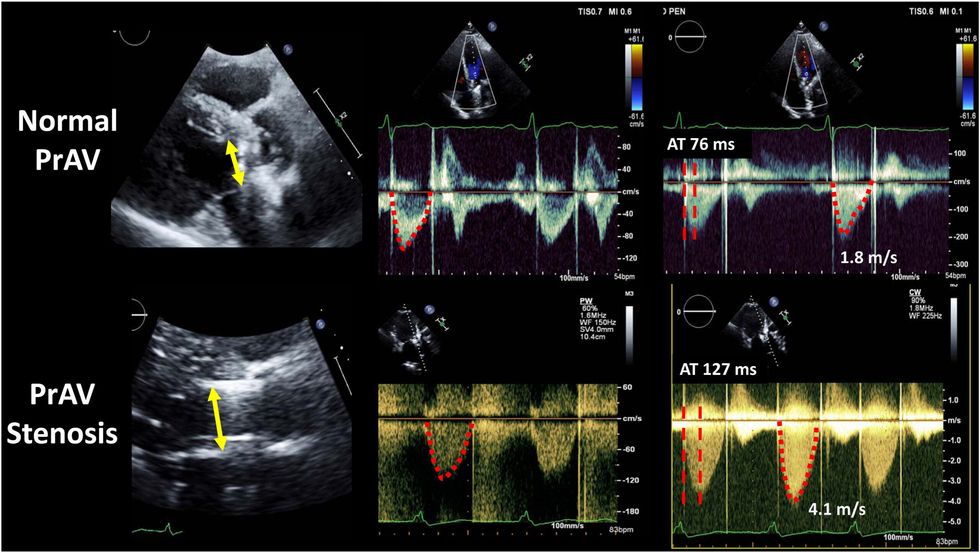

Duke dëgjuar tingujt e zemrës me ndihmën e stetoskopit shfaqet zhurma, e cila mund të ketë një shkallë të ndryshme fuqie dhe përhapjeje. Standardi i artë në diagnostikimin dhe vlerësimin e ashpërsisë së stenozës dhe/ose pamjaftueshmërisë së aortës është ekokardiografia (ekografia e zemrës), e cila mat në kohë reale sipërfaqen e vetë valvulës, shpejtësinë e rrjedhjes së gjakut nëpër vrimën e aortës, si dhe vlerësimi i trashësisë së mureve të barkushes së majtë dhe diametrit të aortës ascendente.

Stenoza e aortës ndodh si rezultat i rrjedhjes së turbullt të gjakut nëpër vrimën e aortës, e cila çon në ndryshime degjenerative që rezultojnë në funksion të pamjaftueshëm të valvulës. Stenoza paraqet një pengesë mekanike për qarkullimin normal të gjakut, prandaj, nëse zgjat më shumë, mund të çojë në trashje të muskujve të zemrës dhe/ose zgjerim (zgjerim) të pjesës fillestare të aortës.

Zgjerimi poststenotik i aortës është një zgjerim i diametrit të aortës ascendente, i cili supozohet se shkaktohet nga rritja e shpejtësisë së rrjedhës nëpër grykën e aortës, si dhe rrjedha e turbullt e gjakut që ndikon në stresin tangjencial të prerjes së murit të aortës, duke shkaktuar rrallimin dhe zgjerimin e tij.